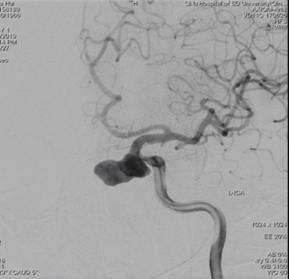

术前造影:

左侧颈内动脉C3段大动脉瘤,大小约23*11mm,瘤颈长度7.4mm,载瘤动脉远端直径约3.8mm,近端直径约4.2mm。